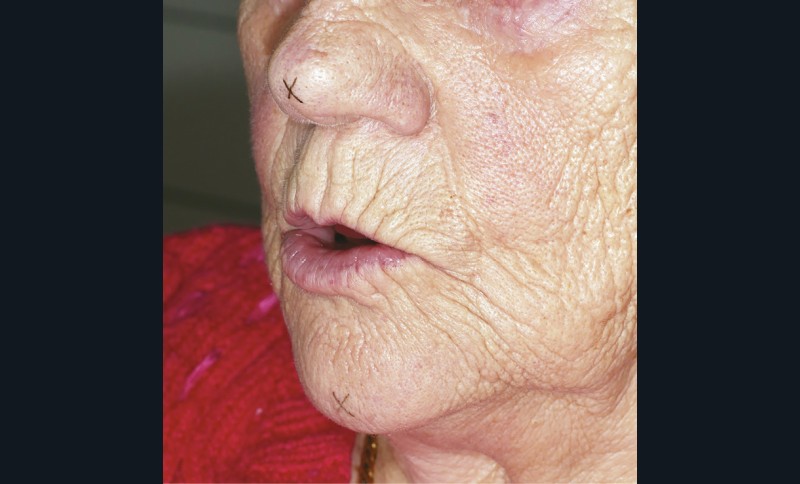

La sous-évaluation, quant à elle, engendre un impact esthétique avec un affaissement de l’étage inférieur de la face. Le patient paraît vieilli, avec un approfondissement des rides et sillons du visage, le menton avance (fig. 2). La déglutition peut être inconfortable, avec une interposition labiale fréquente. Toutefois une légère sous-évaluation engendre peu de conséquences ; le patient aura même tendance à se sentir plus confortable avec ses prothèses.

Les techniques indirectes font appel à la DVR comme variable intermédiaire. Des croix sont tracées au crayon dermographique sur deux points tégumentaires non mobilisables par la mimique (relief antérieur du menton et partie basse de l’arête du nez) (fig. 18). Une fois le patient placé en position de repos, le praticien mesure la distance entre les deux croix tracées à l’aide d’une réglette métallique ou d’un compas à pointe sèche (fig. 19).